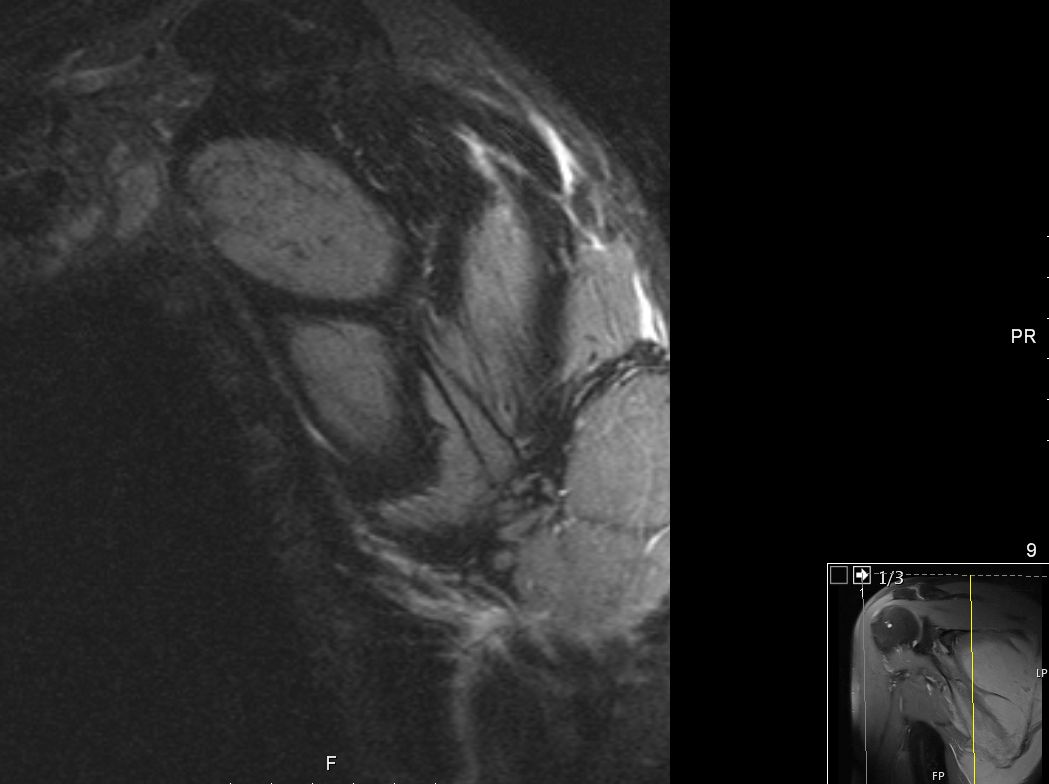

63-jähriger Mann, der vor 5 Jahren eine T - Promyelozyten - Leukämie hatte. Nach ASCT bisher rezidivfrei. Jetzt beschwerden in der rechten Schulter. Das MRT zeigt intramuskuläre Raumforderungen. Die Biopsie ergab Infiltrate der APL.